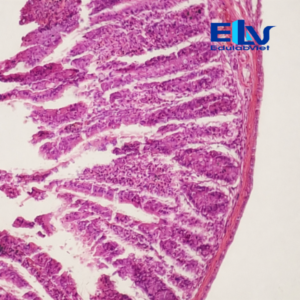

Tiêu bản ruột non cắt ngang là mẫu tiêu bản hiển vi cố định thể hiện rõ cấu trúc vi thể đặc trưng của ruột non như lớp niêm mạc, lông ruột (nhung mao), lớp cơ và các tuyến trong thành ruột. Đây là mẫu tiêu bản quan trọng trong giảng dạy và thực hành môn Sinh học, Giải phẫu học và Mô học.

Quan sát được nhung mao ruột, lớp biểu mô, lớp cơ vòng – cơ dọc và các lớp mô đặc trưng của thành ruột non. -

Tế bào được nhuộm đậm, sắc nét, giúp việc quan sát dưới kính hiển vi quang học trở nên dễ dàng và chính xác. -